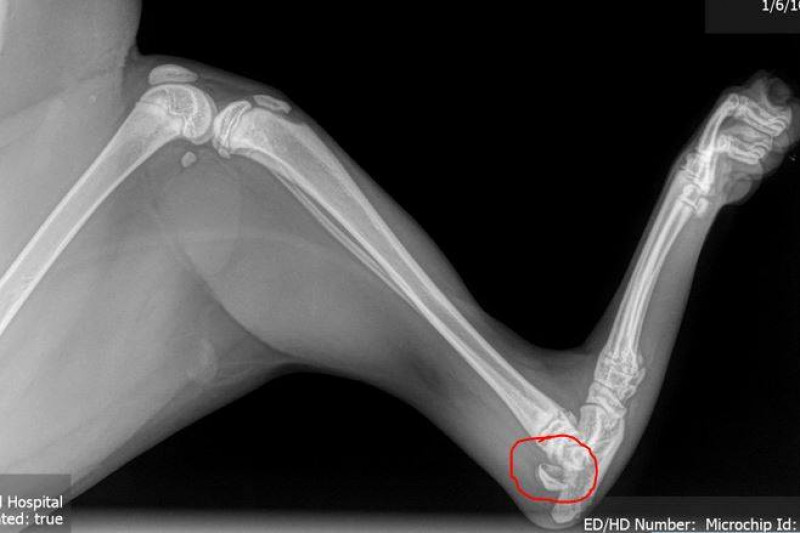

Finlee our 5 1/2 month wheaten Terrier broke her growth plate, surgery

Proximal tibial fracture in a 17week old puppy with open growth plates Dog Growth Plate Surgery What are growth plate injuries? Growth plate fractures seen in immature animals. Puppies have growth plates associated with their long bones that slowly ossify as they grow. Generally pins are used to repair these types of fractures if a type 1 or 2. Surgery for most fractures of the growth plate of the tibia, one or more pins and sometimes. Dog Growth Plate Surgery.